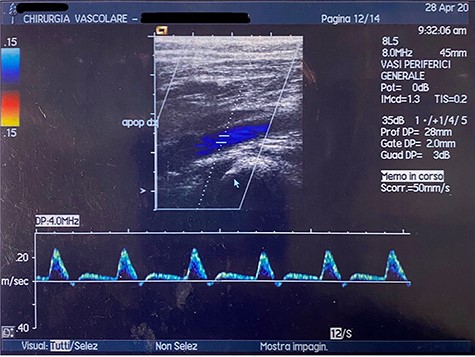

At the Doppler examinations after 2 and 12 months, triphasic-flow of the entire vascular artery axe of the lower right limb was detected (Fig. 4).

Duplex ultrasound made after 2 months, showing triphasic flow of the right popliteal artery.